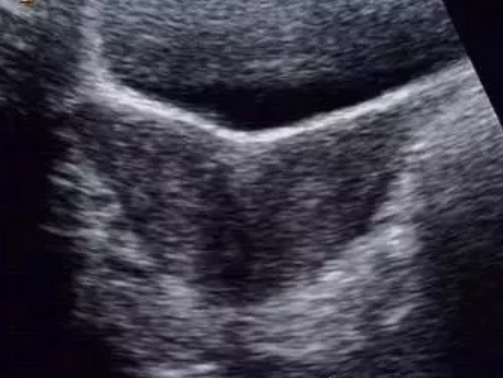

縱隔子宮、雙角子宮都是雙側副中腎管融合不良所致的畸形,在聲像上有很多相似之處,尤其是不完全縱隔子宮與雙角子宮較難鑒別,兩者主要是從子宮外形上予以區別。

雙角子宮是雙側副中腎管尾部已經融合,末端中隔已被吸收,子宮底部融合不良,宮底較寬,兩宮角有一較深外形似羊角的凹陷,兩側各具一宮腔,雙側卵巢多正常。